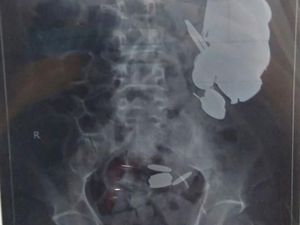

Gulungan Rambut 2,6 Kg Bersarang di Lambung Pengidap Sindrom Rapunzel

Seorang gadis 6 tahun di India mengidap kondisi langka Rapunzel Syndrome. Ia gemar sekali menelan rambut hingga terkumpul seberat 2,6 kg di lambungnya.